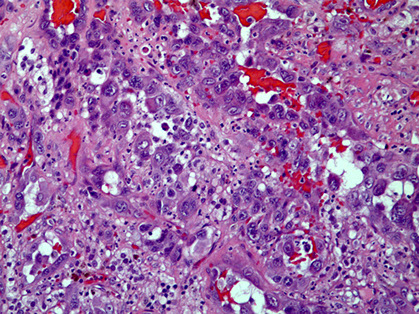

Micro: atypical vascular spaced lined by endothelial cells c atypia and multilayering that involves subQ and has RBCs in intracytoplasmic lumina in more solid areas

- lots of mits and necrosis

IHC: (+) Factor 8 related peptide, CD31, Ki-67, FLI-1, thrombomodulin, CD34, c-kit, VEGFR-3, ERG, INI-1 (is lost in epithelioid sarcoma)